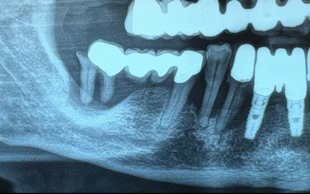

RIALZO DEL SENO MASCELLARE

Il rialzo del seno mascellare è un intervento chirurgico necessario per inserire impianti dentali nei settori posteriori del mascellare superiore quando l’osso è insufficiente. Questa tecnica permette di aumentare lo spessore osseo, mediante l’innesto di biomateriali, creando una base stabile per l'inserimento dell' impianto dentale.

La perdita di denti posteriori può causare un progressivo riassorbimento osseo e un abbassamento del seno mascellare, una cavità naturale vuota rivestita da una membrana epiteliale.

Per compensare questa riduzione, si possono adottare due tecniche:

Mini rialzo del seno mascellare per deficit ossei lievi.

Grande rialzo del seno mascellare per riassorbimenti più significativi.

La scelta della tecnica più adatta dipende dall’altezza dell’osso residuo.